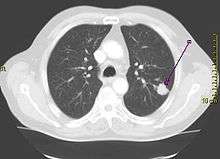

| A chest X-ray showing a tumor in the lung (marked by arrow) | |

The vast majority (85%) of cases of lung cancer are due to long-term tobacco smoking.[7] About 10–15% of cases occur in people who have never smoked.[8] These cases are often caused by a combination of genetic factors and exposure to radon gas, asbestos, second-hand smoke, or other forms of air pollution.[9][7][10][11] Lung cancer may be seen on chest radiographs and computed tomography (CT) scans.[1] The diagnosis is confirmed by biopsy which is usually performed by bronchoscopy or CT-guidance.[12][13]

Diagnosis

Performing a chest radiograph is one of the first investigative steps if a person reports symptoms that may suggest lung cancer. This may reveal an obvious mass, widening of the mediastinum (suggestive of spread to lymph nodes there), atelectasis (collapse), consolidation (pneumonia) or pleural effusion.[1] CT imaging is typically used to provide more information about the type and extent of disease. Bronchoscopy or CT-guided biopsy is often used to sample the tumor for histopathology.[13]

Lung cancer often appears as a solitary pulmonary nodule on a chest radiograph. However, the differential diagnosis is wide. Many other diseases can also give this appearance, including metastatic cancer, hamartomas, and infectious granulomas such as tuberculosis, histoplasmosis and coccidioidomycosis.[61] Lung cancer can also be an incidental finding, as a solitary pulmonary nodule on a chest radiograph or CT scan done for an unrelated reason.[62] The definitive diagnosis of lung cancer is based on histological examination of the suspicious tissue[6] in the context of the clinical and radiological features.[12]